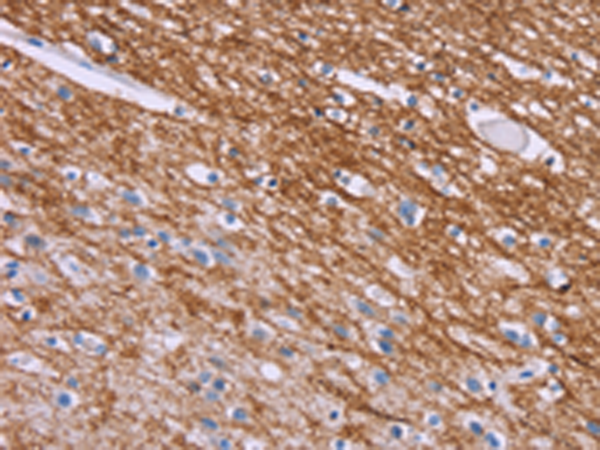

分类: 科研抗体货号: P10764别名: CB1; CNR; CB-R; CB1A; CB1R; CANN6; CB1K5应用: IHC反应种属: Human, Mouse, Rat